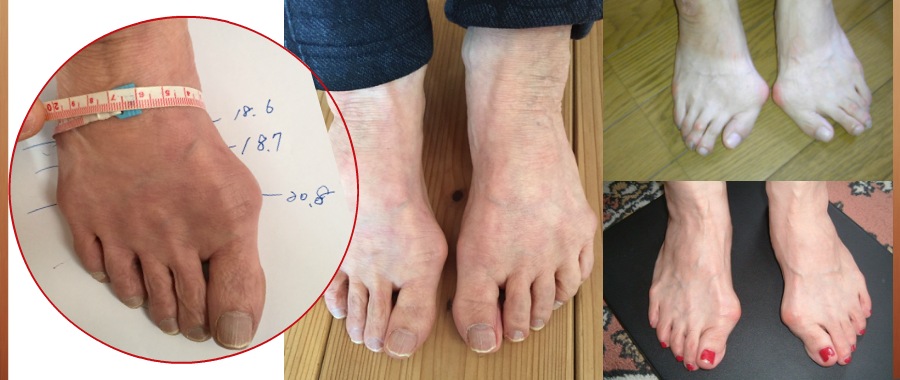

靴に悩む方の足を

その中でも足の形、状態に対応する事はされていません。

外反母趾の害は

外反母趾だけに止まりません。